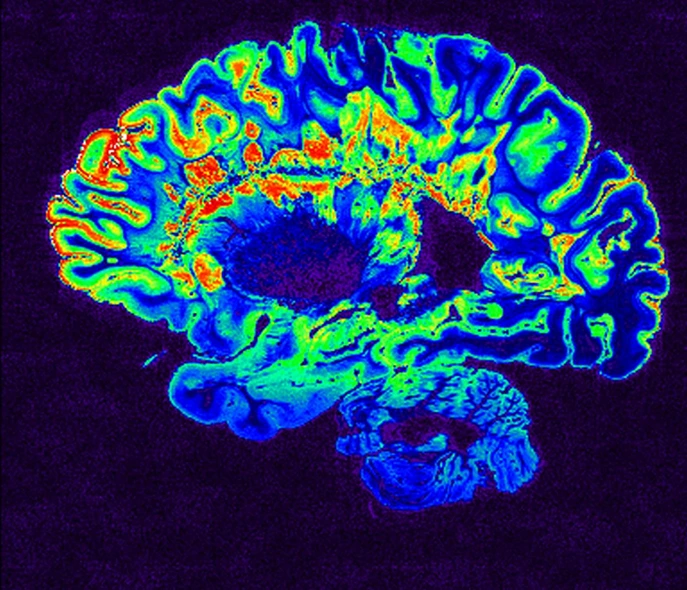

Les aimants naturels sont souvent utilisés à notre avantage dans les applications médicales. Les examens d'imagerie par résonance magnétique (IRM) sont basés sur l'effet de la résonance magnétique nucléaire (RMN). Les noyaux d'hydrogène ont leur propre fréquence naturelle, et si un champ magnétique très puissant est appliqué à l'un d'entre eux, il peut absorber l'énergie des rayonnements électromagnétiques (dans la gamme des radiofréquences) qui est égale à cette fréquence. La désexcitation contrôlée des noyaux d'hydrogène permet de les localiser en fonction du rayonnement qu'ils émettent, ce qui permet de cartographier les tissus du corps en trois dimensions tout en étant non invasif.

L'IRM peut être utilisée pour produire des images du cerveau.